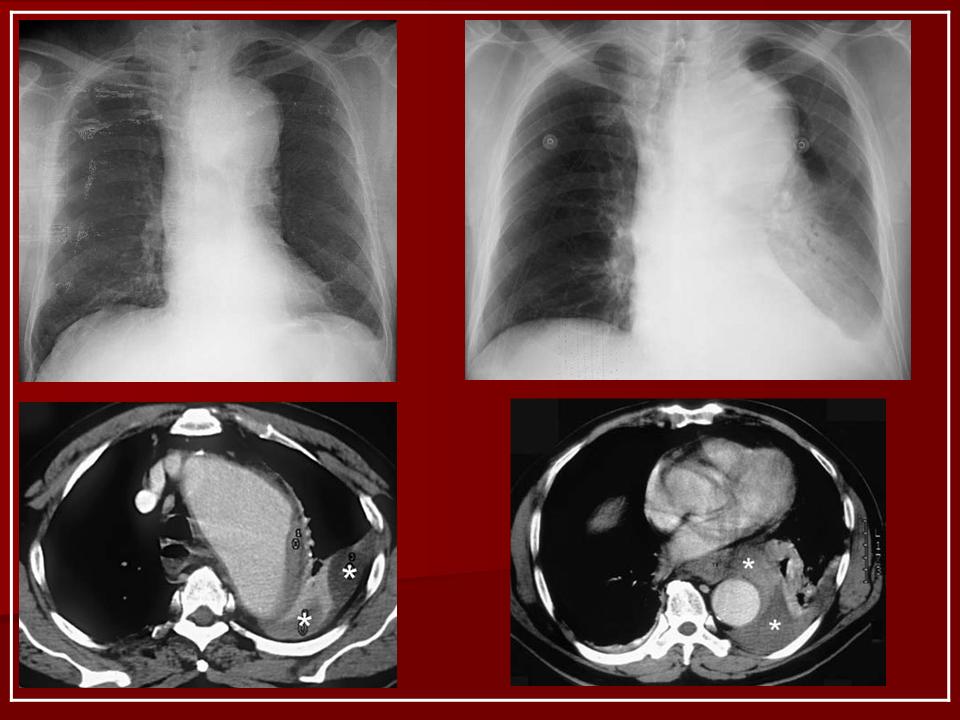

Расслоение аорты

ID: 12384 Aortic dissection with rupture into pericardium Dr Frank Gaillard - 19 Nov 2010 CTA demonstrates a Type A aortic dissection which has ruptured into the ...

ID: 23726 Aortic dissection with rupture into the pericardial sac Dr J. Ray Ballinger - 5 Jul 2013 Aortic dissection is associated with hypertension, Marfan's syndrome and...